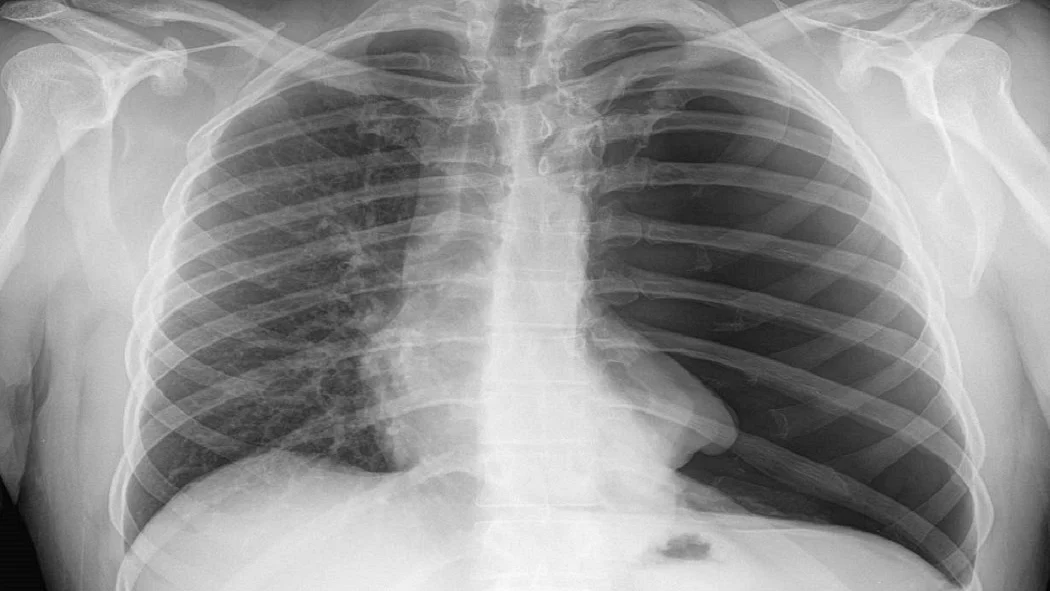

एक और जहां कोरोना वायरस से निपटने के लिए भारत में भी डॉक्टरों और वैज्ञानिकों की टीम दिन रात मेहनत कर रही है। वहीं दूसरी ओर कोरोना वायरस महामारी की जांच में कई तरह की परेशानियों का भी सामना करना पड़ रहा है, लेकिन अब इस परेशानी की समस्या से निजात मिल सकती है। दरअसल, लखनऊ के केजीएमयू और अब्दुल कलाम टेक्निकल यूनिवर्सिटी ने मिलकर आर्टिफिशियल इंटेलिजेंस की बदौलत एक प्रोग्राम तैयार किया है। इस प्रोग्राम के तहत केवल सीने के एक्स-रे से पता चल जाएगा कि मरीज कोरोना संक्रमित है या नहीं।

दरअसल, कोरोना संक्रमित मरीजों की कई जांच रिपोर्ट नेगेटिव आई और बाद में पता चला कि उसे कोरोना संक्रमण है। ऐसे कई केस सामने आए हैं जिनमें कोरोना जांच किट ने कई बार गलत रिपोर्ट दी है। इन समस्याओं को ध्यान में रखते हुए लखनऊ के केजीएमयू और अब्दुल कलाम टेक्निकल यूनिवर्सिटी जांच को और मजबूत बनाने के क्रम में काफी दिनों से शोध कर रहे थे। अब दोनों संस्थानों ने मिलकर आर्टिफिशियल इंटेलिजेंस की बदौलत एक प्रोग्राम तैयार किया है। जिससे सिर्फ सीने यानी छाती का एक्स-रे देखकर यह पता चल पाएगा कि मरीज कोरोना संक्रमित है या नहीं।

किंग जॉर्ज मेडिकल यूनिवर्सिटी ने प्रदेश के कई जिलों से कोरोना वायरस से संक्रमित मरीजों की छाती का एक्स-रे मंगाकर इस पर काम शुरू कर दिया है। अब ये जल्द ही क्लीनिकल ट्रायल में जाएगा। लखनऊ के केजीएमयू हॉस्पिटल ने बकायदा एक प्रेस कॉन्फ्रेंस करके इस बात की जानकारी दी है। प्रेस कॉन्फ्रेंस में कहा गया कि चीन और अमेरिका के बाद केजीएमयू जल्द ही एक्स-रे देखकर कोविड मरीजों की पहचान करेगा। एक्स-रे से ना सिर्फ कोविड मरीजों का पता चलेगा बल्कि फेफड़े के संक्रमण से यह भी पता लग पाएगा कि मरीज कब और कितनी जल्दी ठीक हो सकता है। बता दें कि जब चीन में रैपिड टेस्ट कम हो रहे थे तो आर्टिफिशियल इंटेलिजेंस का यह तरीका कारगर साबित हुआ था। इस मॉडल में कोविड-19 रोगियों की पहचान करने का काम अमेरिका, ब्रिटेन, चीन और कुछ अन्य देशों भी कर रहे हैं। अब जल्दी भारत में केजीएमयू में यह शुरू होने जा रहा है।